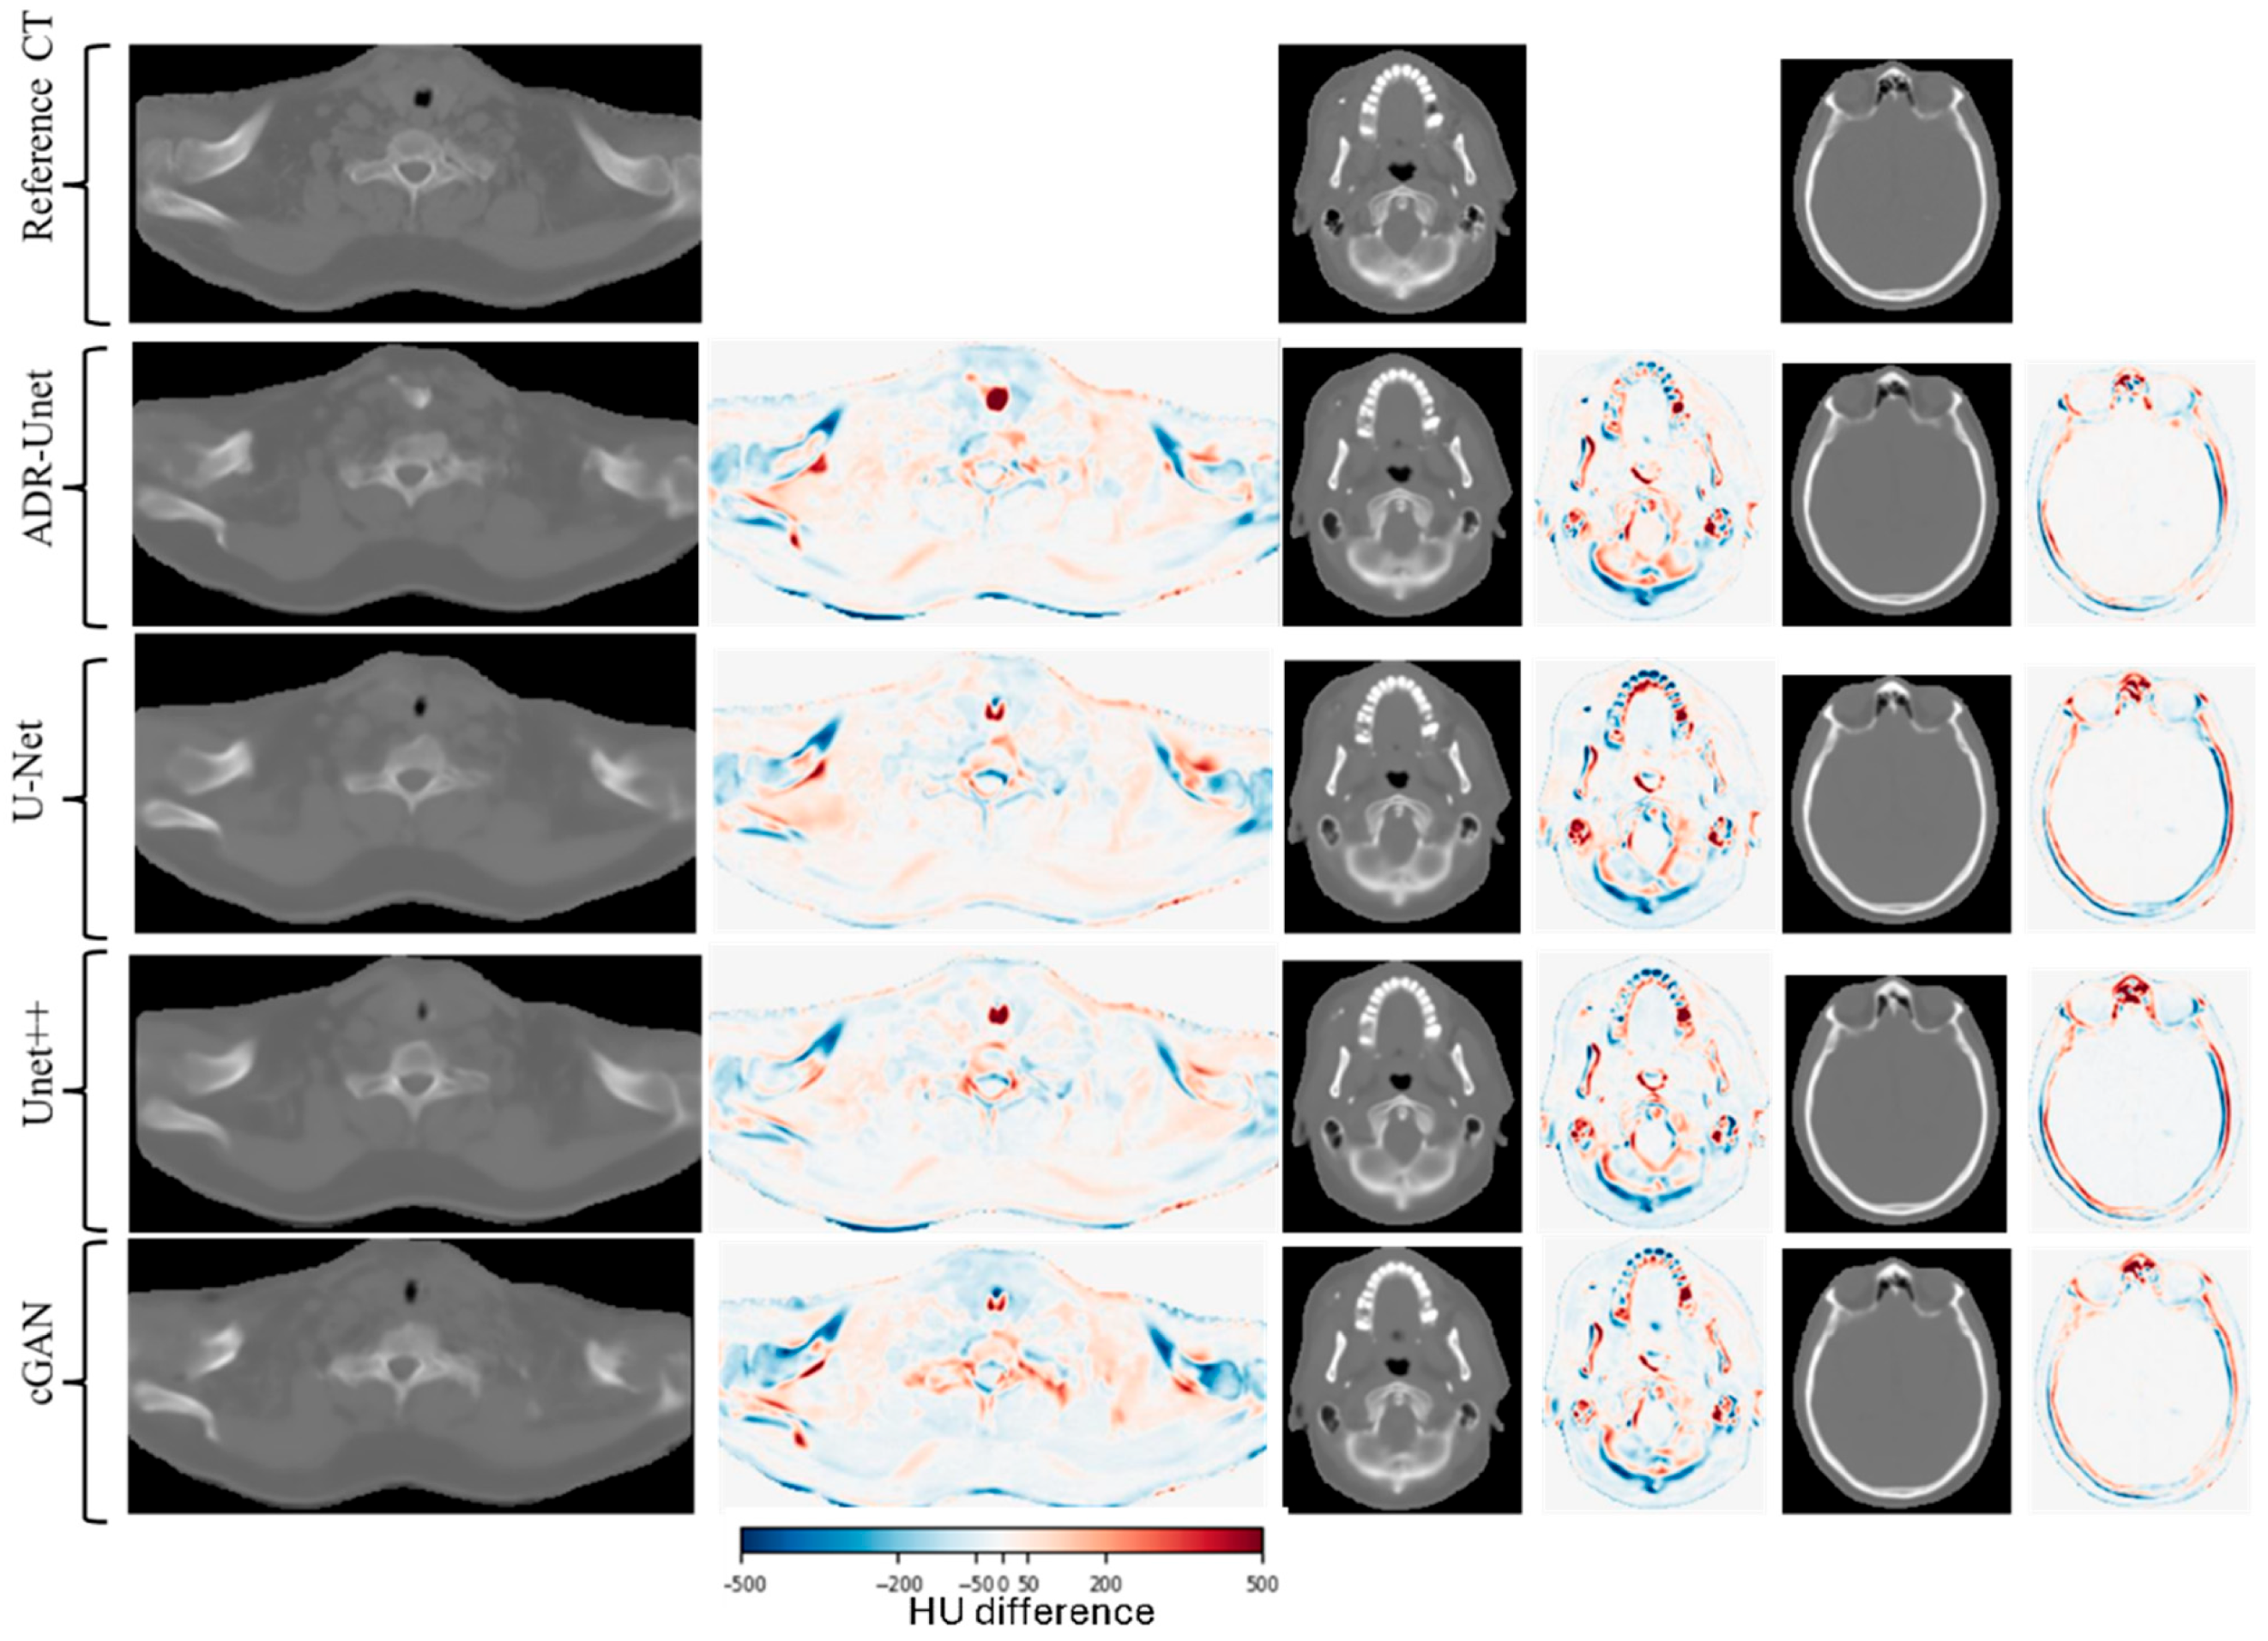

3. Results

3.1. Parameters Selection

3.3. Image Quality Assessment of Attention Deep Residual U-Net

| Error Type | ADR-Unet | cGAN | Unet | Unet++ |

|---|---|---|---|---|

| MAE [HU] | 55.49 ± 7.79 | 57.66 ± 10.44 | 60.06 ± 10.94 | 59.32 ± 7.09 |

| ME [HU] | −1.75 ± 7.62 | −4.57 ± 17.59 | 2.77 ± 13.31 | 0.25 ± 10.40 |

| PSNR [dB] | 56.07 ± 0.87 | 55.95 ± 1.51 | 55.77 ± 1.45 | 55.89 ± 0.72 |

| SSIM | 0.99 ± 0.00 | 0.99 ± 0.00 | 0.99 ± 0.00 | 0.99± 0.00 |

| Gamma pass rate [%] | 99.4 ± 0.26 | 99.6 ± 0.18 | 99.5 ± 1.85 | 99.4± 1.63 |